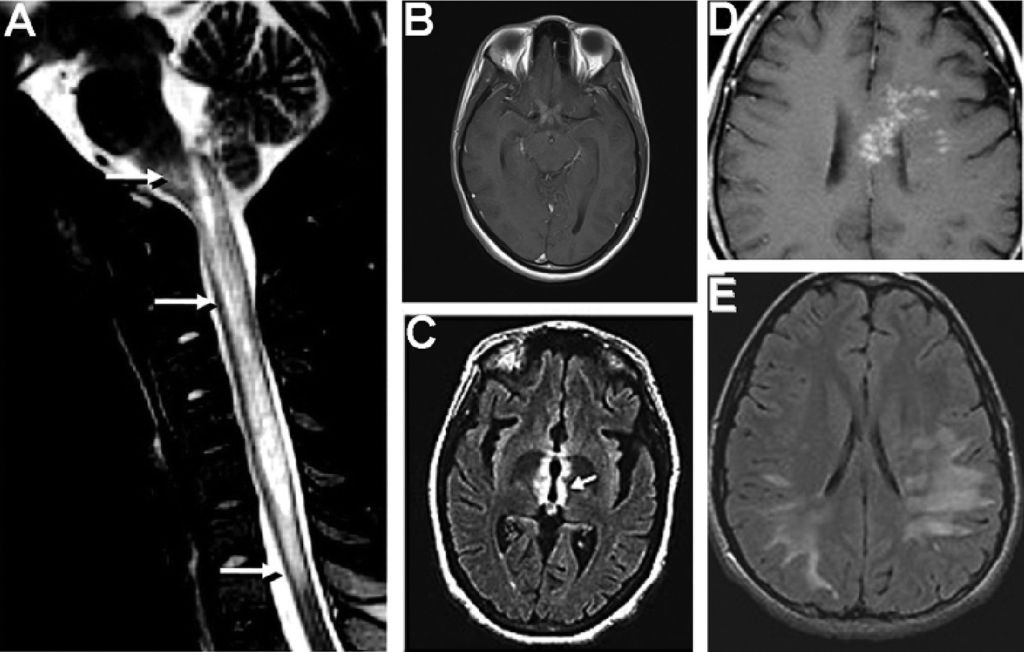

Neuromyelitis optica (NMO), also known as Devic’s disease, is a rare condition that affects the spinal cord and the nerves of the eyes (optic nerves). It can cause a wide range of symptoms, such as weakness, blindness, nerve pain and Cyclical vomiting.

In November 2017, I woke up one day getting ready for school and felt very off balance. Being me, I decided to ignore it and carry on with the day. I remember being at school and feeling the worst shooting pain at the back of my eyes. Things started to slowly look ashy and black; I felt dizzy and sick. No one knew what was going on. My mum and I decided to take a trip to ophthalmology to see whether my eyes were healthy and okay, as this shooting pain didn’t leave. I remember the doctor saying to me, “Runako, your eyes are healthy.” However, I was experiencing a series of serious migraines, so the ophthalmologists advised us to go to A&E that night. They took a series of blood tests and ECGs, but furthermore, they could not find anything wrong with my body. I was given an appointment for an MRI, and the results showed that I had inflammation of the optic nerve, but no actions were taken at the time. My vision started to deteriorate over the months from November 2017 until February 2018, where I battled through my Year 11 school year while having severe medical issues. My vision kept deteriorating, and no doctor or consultant could diagnose me with a condition.